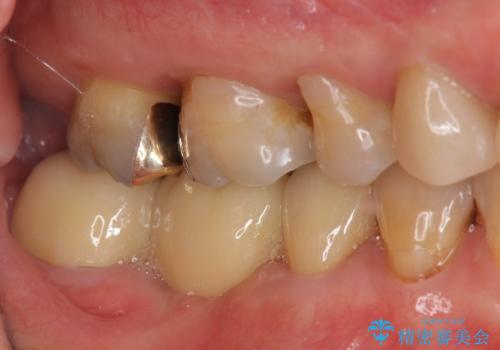

- 右下奥歯からの排膿、痛みの改善を希望され来院されました。

薄い歯質の歯牙に過大な負荷がかかり亀裂を生じ大臼歯分岐部に大きな骨吸収を認め、抜歯を余儀なくされる状態です。

抜歯を行ったのち前後の歯に軽度の動揺があるため、インプラントではなくブリッジによる補綴処置を行い機能回復を行いますが、近心傾斜した第2大臼歯をマイクロインプラントを用いた小矯正を行うことで歯軸方向を改善し、神経を温存した状態でブリッジ製作できるよう前処置を行います。